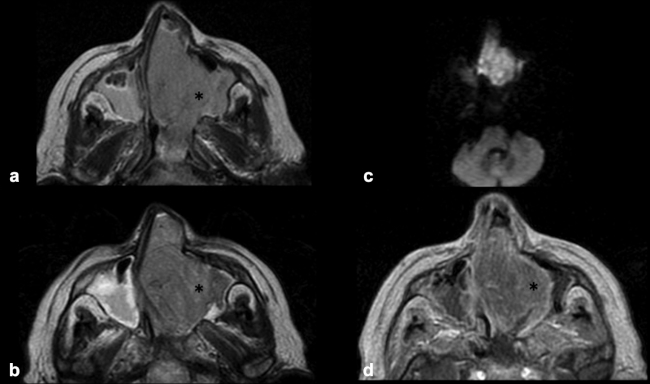

La TC de corte fino (espesor de corte de 1 mm) con reconstrucciones en plano coronal y sagital, es la mejor prueba de imagen inicial para el estudio del NBO. En la TC, aparece como una masa homogénea de tejido blando en la bóveda nasal con realce moderado y uniforme (►Figs.1y2). Se pueden encontrar calcificaciones punteadas dispersas (►Figs.2,3,4,5a,6).50 El valor principal de la TC es una mejor definición de la afectación ósea en comparación con la RM. La TC ayuda a evaluar la erosión ósea de la placa cribiforme, la fóvea etmoidal y la lámina papirácea (►Figs.1,2,3,4,5a,8). Sin embargo, la remodelación ósea sin erosión puede presentarse en algunos casos debido a su patrón de crecimiento indolente.3,35,49 Los estudios de TC generalmente revelan un patrón lítico y muy raramente hiperostosis dominante que simula displasia fibrosa.51 La TC también es útil para evaluar la presencia de metástasis regionales en cuello y a distancia.52,53

La RM es la prueba de imagen de elección para evaluar los detalles de la extensión y la estadificación locorregional del tumor. La RM es superior a la TC para determinar el grado de afectación del tejido blando (►Fig. 9) con una mejor evaluación de la afectación intracraneal (►Figs.10,11,12,13,14), orbital (►Figs.14y15), de la base del cráneo y la invasión perineural.53,54 La RM tiene un valor añadido para distinguir la afectación dural de la del parénquima cerebral (►Fig. 12).55 En la RM, el NBO aparece hipointenso respecto a la sustancia gris en imágenes ponderadas en T1 y de isointenso a hiperintenso en las imágenes ponderadas en T2 (►Figs.10,11,12,13,14,15).56 Muestra un realce homogéneo, excepto en áreas con hemorragia o necrosis. Además, permite diferenciar las secreciones retenidas del tumor, al ser estas hiperintensas ponderadas en T2.53,55 Los hallazgos de imágenes clásicos incluyen una masa “en forma de mancuerna” que se extiende a través de la placa cribiforme (►Fig. 12), con la parte estrecha a nivel de la placa. Los quistes tumorales periféricos (►Figs.5b,12,14,16) y las calcificaciones moteadas son bastante característicos de NBO.1